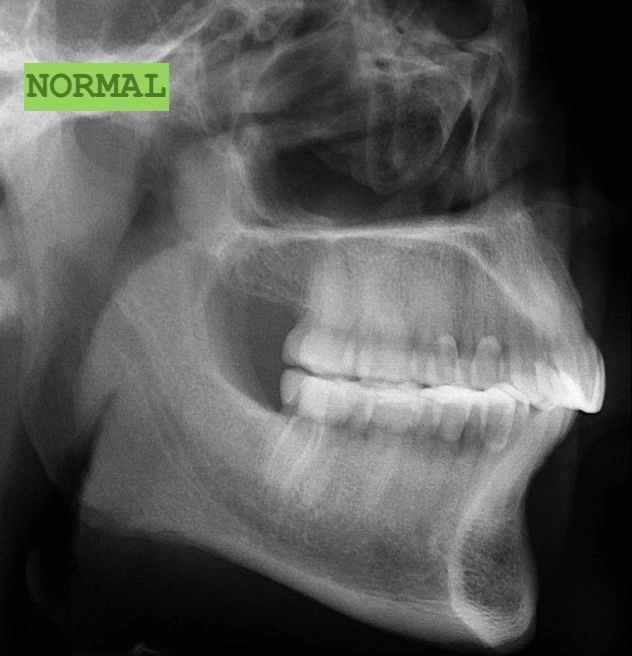

1. The Deep Bite: When Your Child’s Teeth Don’t Line Up Right

One of the most common problems I see is a deep bite.

This is a vertical issue where the upper teeth overlap the lower teeth so much that you can’t even see the bottom teeth.

Sounds concerning, right? Let’s break it down.